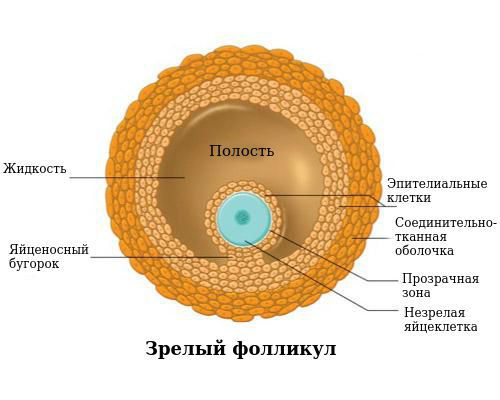

Созревание фолликула в яичнике: этапы и процессы